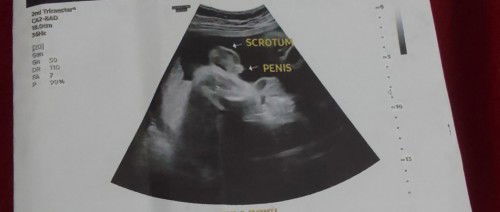

Boy or girl?

Hi pOH. Tanong lng po Ako boy po ba talaga? Thank u po sa mka sagot🥰🥰 #First_Baby

Ultrasound 1

Hi po pwede magtanong kng naka pa ultrasound na po pwede na bang Hindi magpa ultrasound ulit. ? #1stimemom #advicepls #pleasehelp #pregnancy #pregnancy